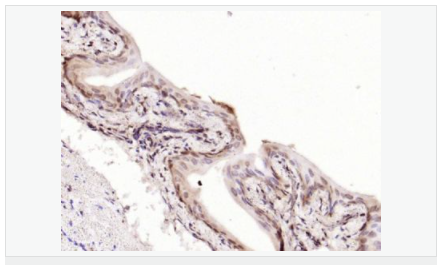

| 產(chǎn)品應(yīng)用 | WB=1:500-2000 ELISA=1:5000-10000 IHC-P=1:100-500 IHC-F=1:100-500 Flow-Cyt=1μg /test IF=1:100-500 (石蠟切片需做抗原修復) not yet tested in other applications. optimal dilutions/concentrations should be determined by the end user. |